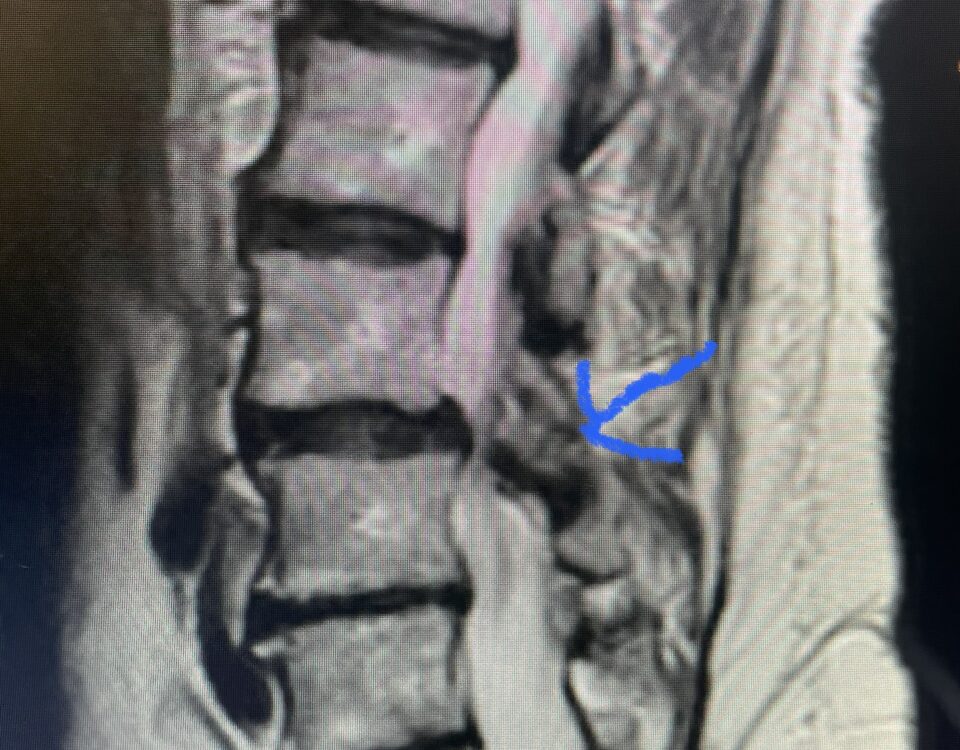

Nervous tissue is soft. The thecal sac is surrounded by a rigid bony ring which forms the spinal canal. Any mass that fills the very small […]